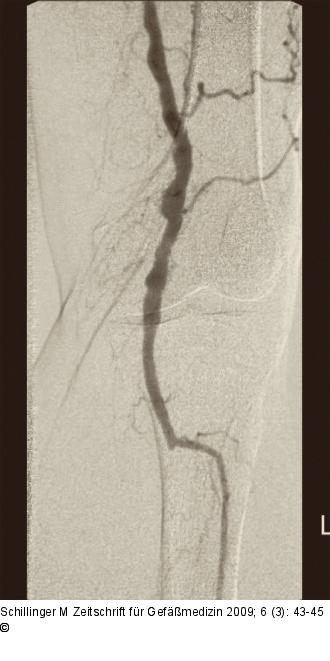

Abbildung 3: Arteria poplitea Abstrom über die Arteria poplitea und ein Unterschenkelgefäß. |

Abbildung 3: Arteria poplitea

Abstrom über die Arteria poplitea und ein Unterschenkelgefäß. |